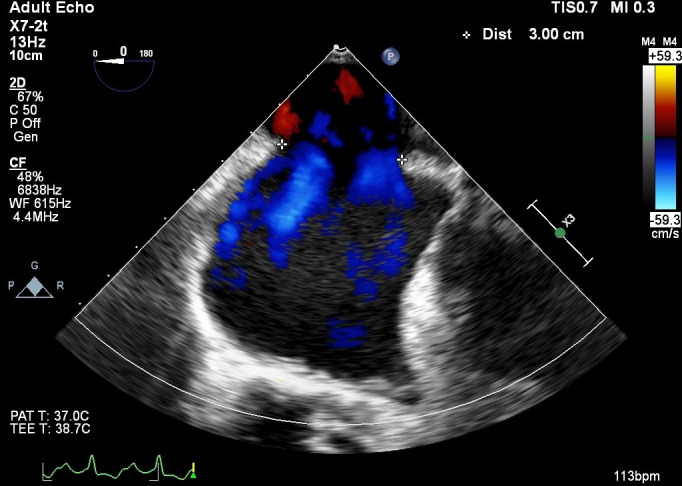

Arterial blood gas taken under room air showed type 1 respiratory failure, potential of hydrogen (pH): 7.48, partial pressure oxygen: 61, partial pressure carbon dioxide: 28, bicarbonate: 23, base excess: −2.6. Admission ECG showed sinus tachycardia, right axis deviation, P pulmonale, partial RBBB with Crochetage sign-notched R wave in II, III, aVF, right ventricular strain picture with ST depression and T inversions in II, III, aVF (figure 1). Transoesophageal echocardiography showed secundum ASD of 3 cm with bidirectional shunt, blood clot in the right pulmonary artery and sign of pulmonary hypertension (figures 2–4). Chest radiograph showed cardiomegaly, dilated pulmonary artery and increased pulmonary vascular markings (figure 5). We proceeded with CT pulmonary angiogram which revealed a long segment eccentric chronic thrombus in the right main pulmonary artery and the ascending and descending right pulmonary arteries. There was also a filling defect in the left pulmonary artery extending to the left superior pulmonary artery in keeping with thrombosis. Further history showed no other risk factor of pulmonary embolism (Figure 6).

Figure 2.

Atrial septal defect measuring 3 cm in size.